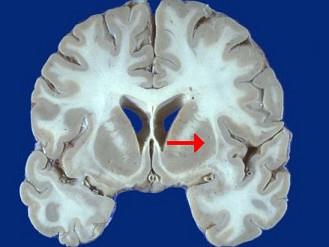

如图箭头所示为大脑哪个部位 ( )A、内囊B、齿状核C、丘脑D、尾状核E、壳核一、单项选择题

问题 如图箭头所示为大脑哪个部位 ( )

选项 A、内囊 B、齿状核 C、丘脑 D、尾状核 E、壳核 一、单项选择题

答案 E